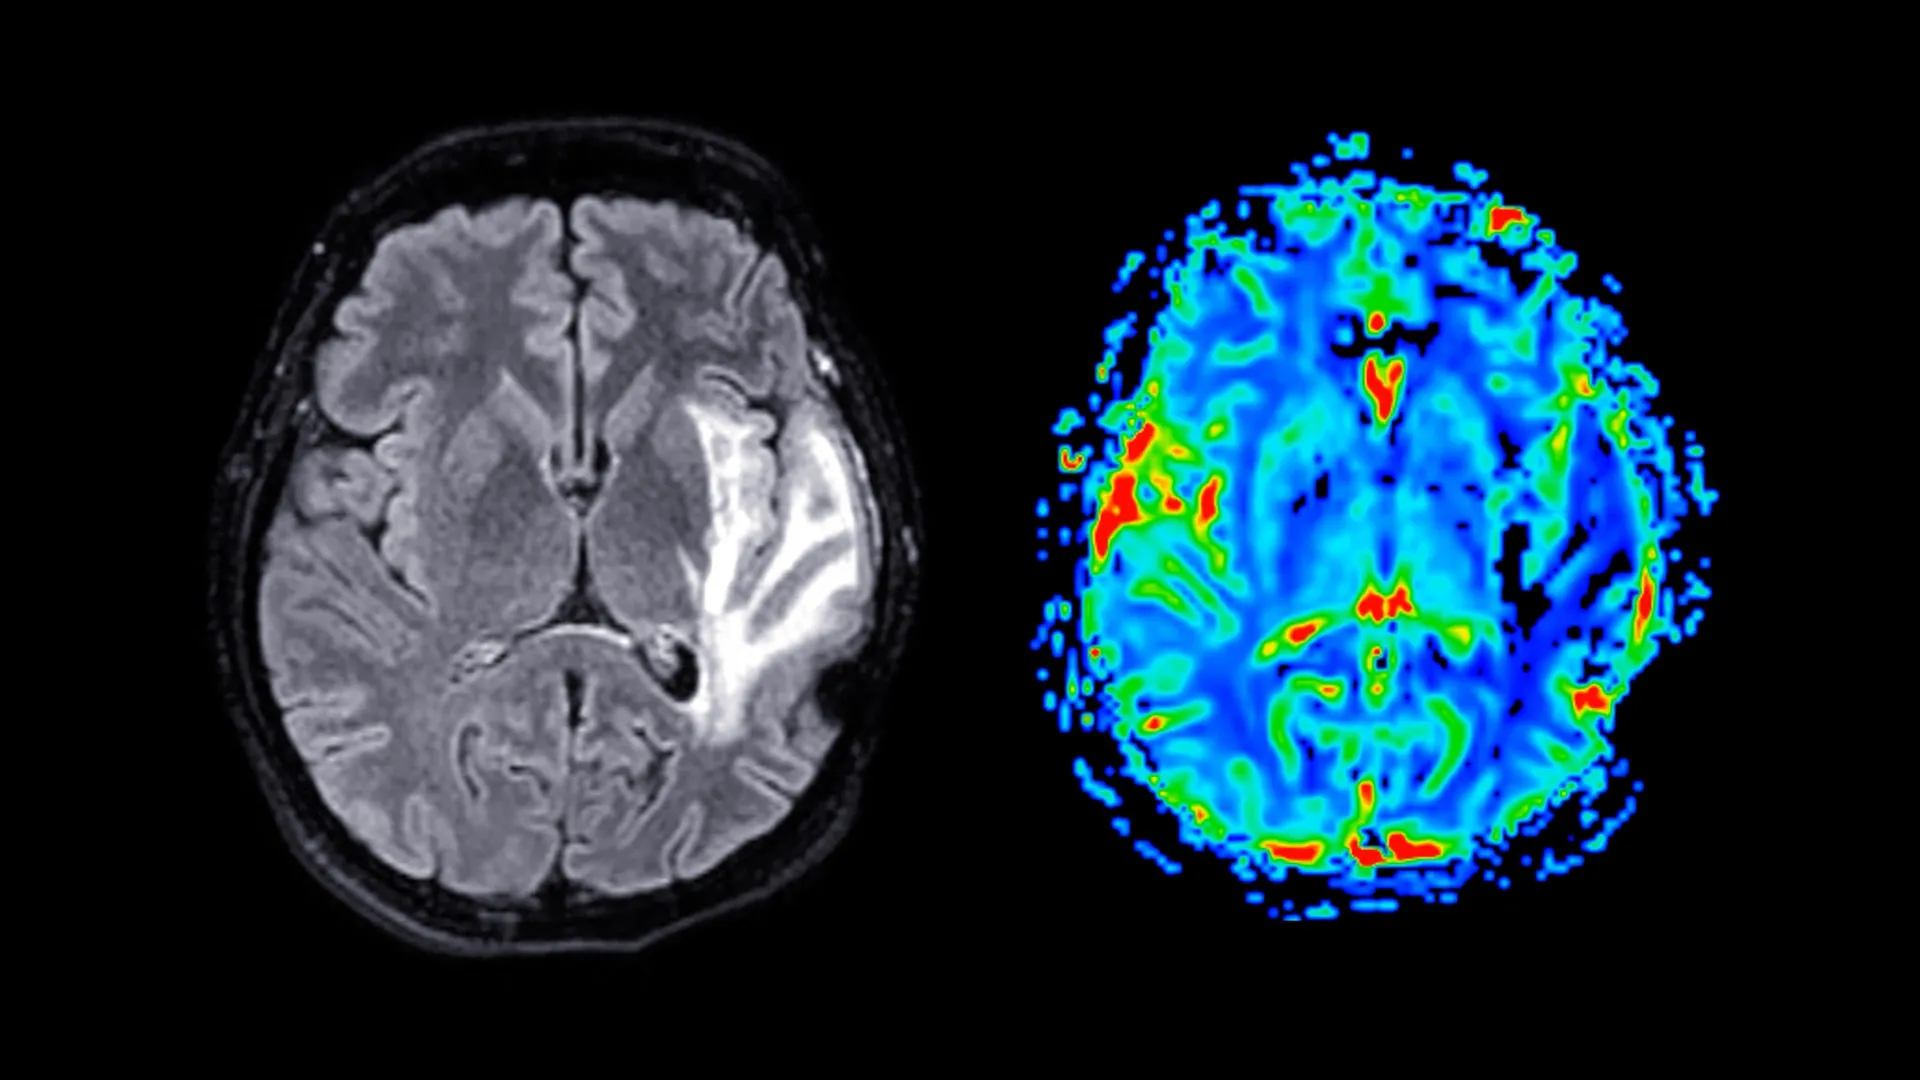

A demência é uma preocupação crescente de saúde pública global, e atualmente não existe cura. Indivíduos afetados pela condição enfrentam um sério declínio nas habilidades mentais, incluindo memória, raciocínio e pensamento, o que pode afetar significativamente a vida cotidiana.

Demência refere-se a um conjunto de distúrbios cerebrais, e não a uma única doença. As formas mais comuns incluem a doença de Alzheimer, demência vascular e demência mista. Essas condições danificam gradualmente as células nervosas no cérebro, e os sintomas pioram com o tempo. À medida que a doença avança, as pessoas podem ter dificuldades com memória, linguagem, resolução de problemas e alterações no comportamento.